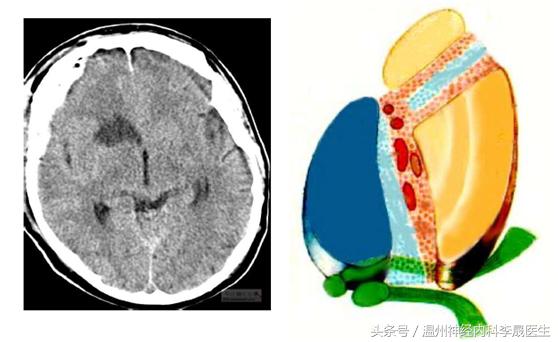

附上一组经典的CT片跟MRI片

首先看看前动脉的供血区域,左图红色,右图绿色区域就是大脑前动脉的供血区域